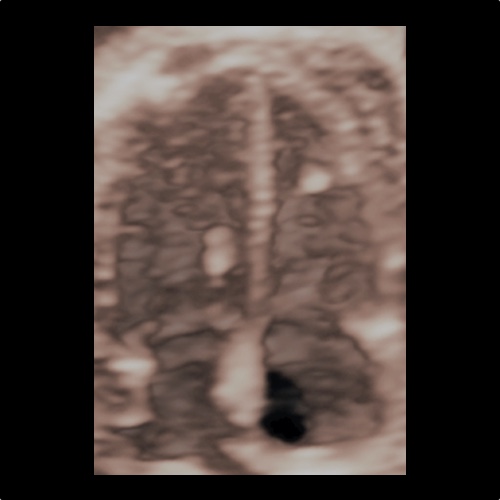

Ecocardiografia fetale 3D

Ecocardiografia fetale